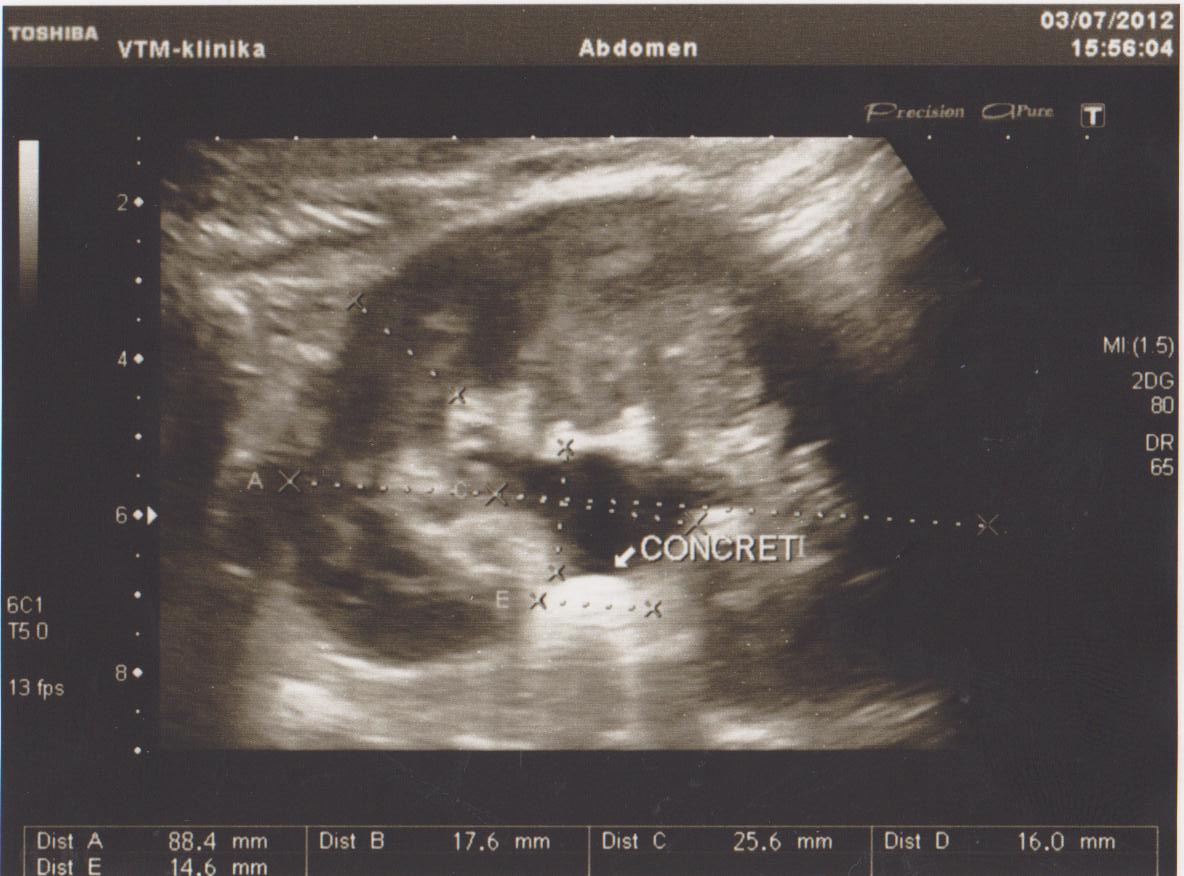

Ниже я привел пару УЗИ снимков из практики, все они есть в галерее УЗИ на сайте, смотрите и не пугайтесь: